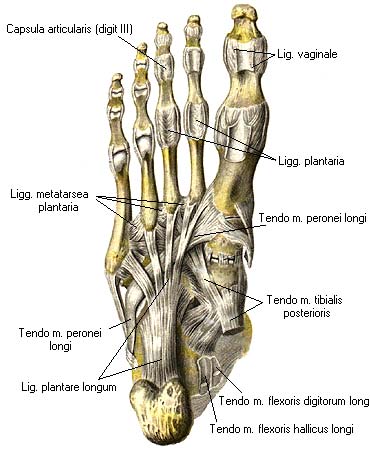

Анатомия голеностопа: Сухожилия и их строение